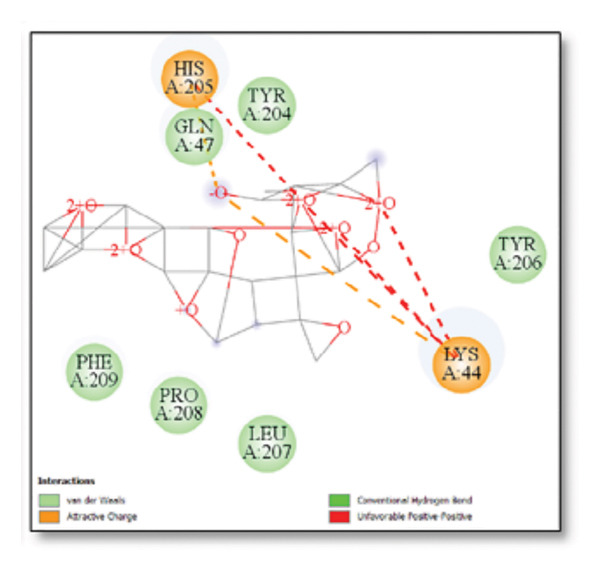

3.3. AutoDock Vina Results: Clusterin Receptor

Ginkgolide showed the strongest binding at −13.98 kcal/mol, interacting with HIS205. Other potent ligands were ginsenosides (−8.02 kcal/mol), which formed contacts with PHE240, and berberine (−6.46 kcal/mol), interacting with ASN291. Resveratrol also exhibited favorable binding (−6.34 kcal/mol), forming H‐bonds with PRO212 and ALA373. Cannabidiol had the weakest binding at −3.56 kcal/mol, interacting with ARG292:HE1. The weakest binder was cyanidin (−3.92 kcal/mol), which showed no hydrogen bond interactions.

For reference drugs, donepezil (−5.65 kcal/mol) with GLY378, Figure 3 illustrates the binding characteristics of natural ligands and reference drugs for the clusterin receptor.

The in silico predictions for ginkgolide’s interactions with sortilin, clusterin, and tau are well‐supported by the established structural and functional mechanisms of these proteins in scientific literature. For sortilin, the predicted interaction with ARG292 and TYR318 is consistent with the protein’s known structure. Studies have shown that its large, ten‐bladed β‐propeller domain is the primary ligand‐binding site; ARG292, often positioned near the VPS10P domain, likely provides critical electrostatic stabilization, while TYR318 contributes $\pi‐\pi$ or $\pi$‐cation interactions, collectively stabilizing the ligand–receptor complex. This binding site overlaps with regions known to undergo conformational change during ligand recognition, suggesting ginkgolide may allosterically modulate the receptor’s trafficking function. A 2017 study by [ref. 38], for example, demonstrated how conformational changes in this domain, caused by pH, disrupt binding sites. Similarly, a review by Quistgaard et al. [ref. 39] highlights how the architecture of the VPS10 domain, which includes these residues, is vital for its function. For clusterin, the predicted interaction with HIS205 is supported by the protein’s established role as a molecular chaperone that prevents protein aggregation.

Histidine residues are frequently involved in coordinating chaperone‐substrate interactions. The binding of ginkgolide at HIS205 suggests it may stabilize the active conformation of the chaperone, thereby enhancing its ability to bind to and inhibit the formation of amyloid fibrils, a key mechanism reinforced by recent research published [ref. 40]. This research has consistently reinforced that clusterin’s ability to bind to and inhibit the formation of amyloid fibrils is a key mechanism of action, particularly in neurodegenerative diseases. While direct mention of HIS205 is rare, its chaperone function is broadly understood to rely on such key residues. Elias et al. [ref. 41] and Carini et al. [ref. 42] confirm that clusterin’s role in inhibiting aggregation is a major focus of current research. Finally, the predicted binding to HIS329 in tau is highly significant and directly corroborated by recent literature. HIS329 is explicitly located within the microtubule‐binding repeat domain, which is the primary site for tau’s pathological self‐aggregation. Ginkgolide’s predicted binding at this position is a direct mechanism of aggregation inhibition, suggesting it acts as a steric wedge or “capping agent” to prevent the formation of toxic beta sheet structures, aligning with similar strategies explored. Studies have explicitly identified histidine residues within the microtubule‐binding repeat domain as participants in tau’s self‐aggregation process. Hernández et al. [ref. 43] specifically names residues like H329 as being involved in this mechanism. Molecular docking and simulation studies, such as one from 2025 by Saha and Natarajan [ref. 44], also focus on targeting this domain with small molecules to inhibit tau pathology, providing strong support for the in silico predictions.